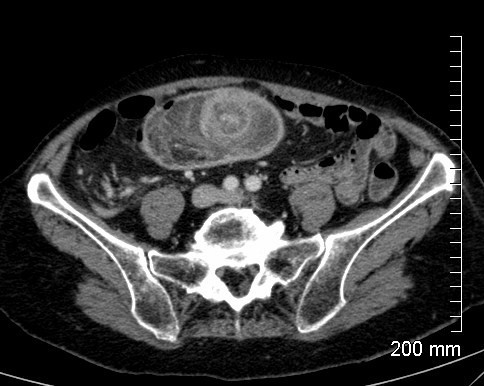

Patient de 75 ans, affaibli, se présente aux urgences pour syndrome occlusif après une période d’alternance diarrhée/constipation. Pas de vomissements, météorisme abdo, arrêt des matières et des gaz depuis 24h. Diagnostic?

Occlusion colique mécanique pariétale: tumeur colique